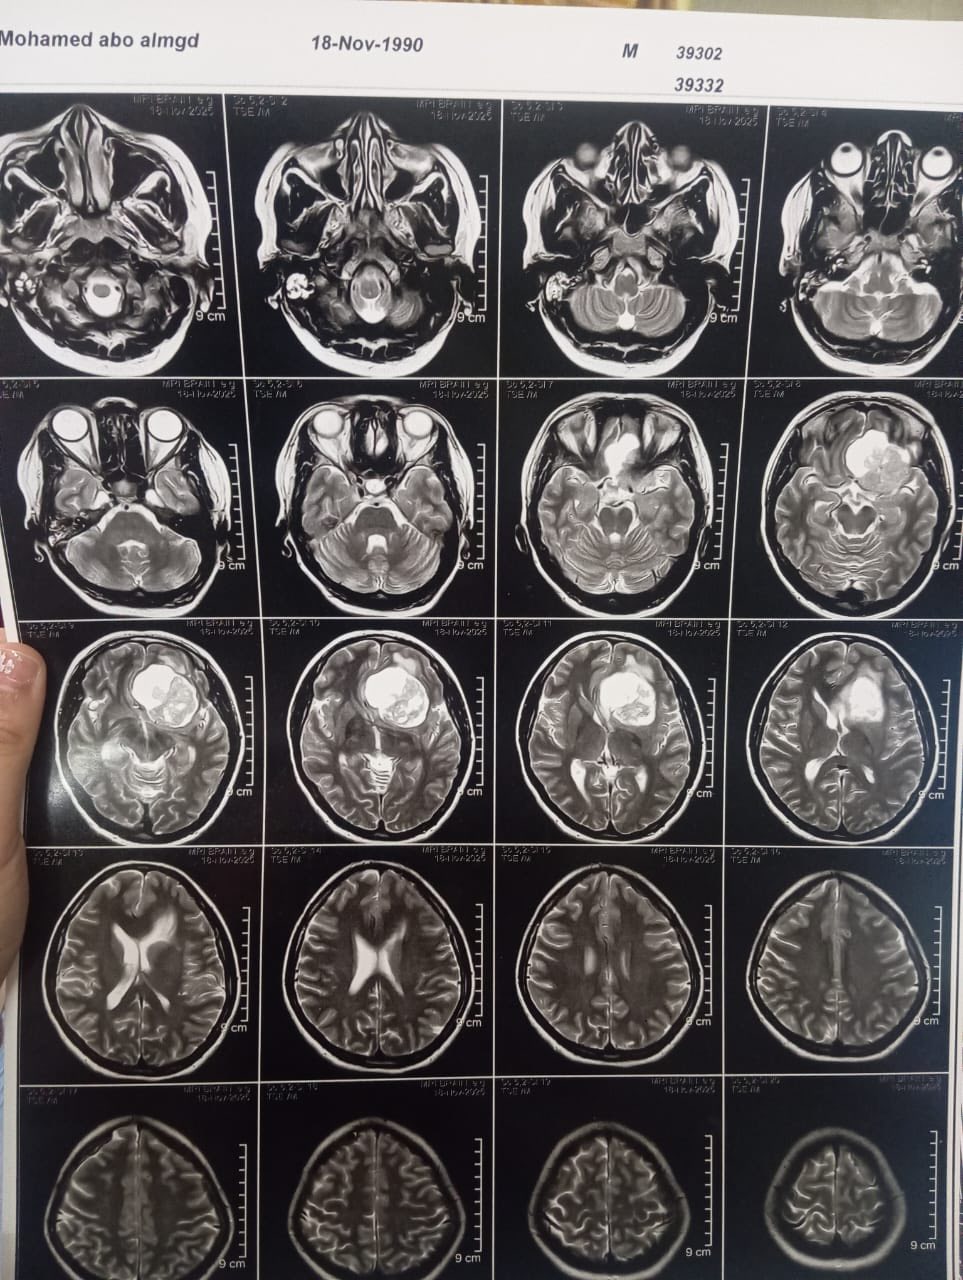

ومن جانبه، أوضح الدكتور مجدي القاضي، عميد كلية الطب البشري، ورئيس مجلس إدارة المستشفيات الجامعية ، أن المريضة حضرت وهي تعاني من صداع شديد وارتفاع بضغط المخ مع تدهور ملحوظ في حدة الإبصار، وبإجراء الفحوصات الطبية اللازمة وأشعة الرنين المغناطيسي، تبيّن وجود ورم كبير بقاع الجمجمة ضاغط على أعصاب البصر والأوعية الدموية المغذية للمخ، ما استدعى التدخل الجراحي العاجل باستخدام أحدث التقنيات الدقيقة.